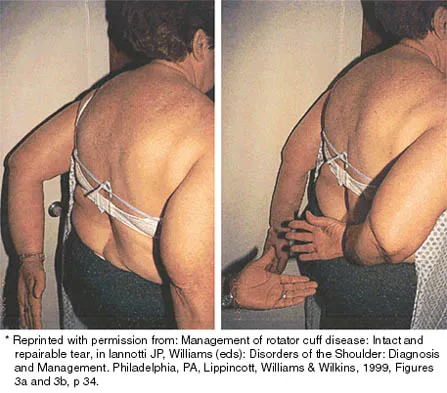

A 43-year-old bus driver sustains a hyperextension injury to her arm and shoulder 4 months after undergoing an open Bankart repair. Examination reveals increased external rotation, anterior shoulder pain, and internal rotation weakness. Her examination also reveals the findings shown in Figure 44. What is the most likely diagnosis?